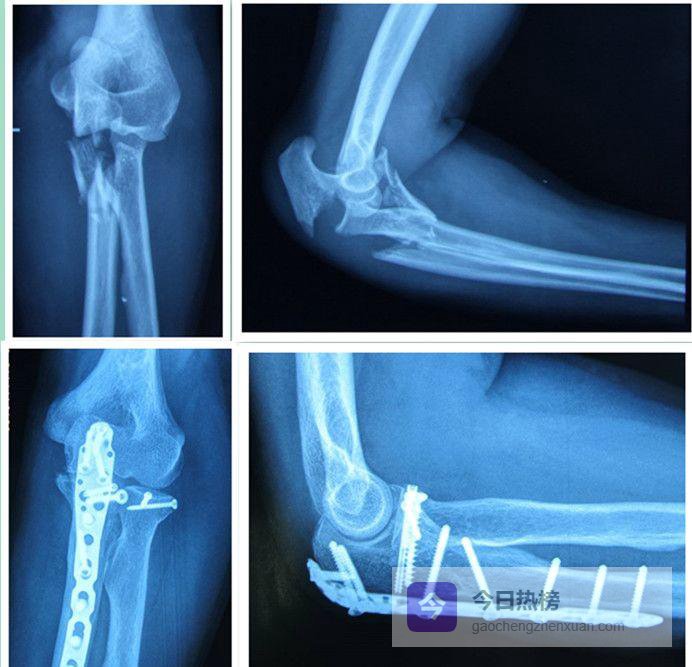

02复杂肘关节骨折:到底“复杂”在哪?

单纯脱位只是“软组损伤”,复位后多数能安稳度日;一旦合并桡骨头、冠状突或尺骨鹰嘴骨折,就升级为“复杂肘关节脱位”。这些“关键零件”碎成几块,就像拼图少了关键几片,后期出现慢性不稳、关节退变的风险陡增。

03手术策略:从“拼图”到“重建”

3.1 ❒ 复位原则——先拼“同心圆”术中优先恢复肘关节的同心圆解剖:尺骨长度、肱桡关系、肱尺匹配一个都不能错。所有小碎片都应力争解剖复位,桡骨头、冠状突更是“能钉就钉”。医生需要踩准“力学节奏”——先固定哪块、后固定哪块,完全取决于骨折类型与受力方向。

3.3 ❒ 固定技巧——从“钢丝”到“钢板”从桡骨头小碎片到冠状突凹面骨折,不同部位要用不同“工具箱”:拉力螺钉、锁定钢板、可吸收钉……选错固定物就像用错螺丝刀,轻则松动,重则内固定失败。